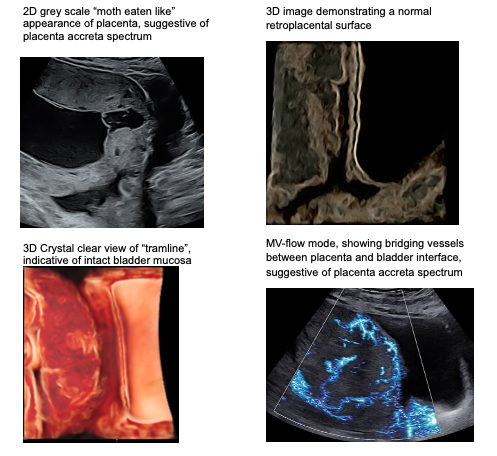

Placenta Accreta Spectrum